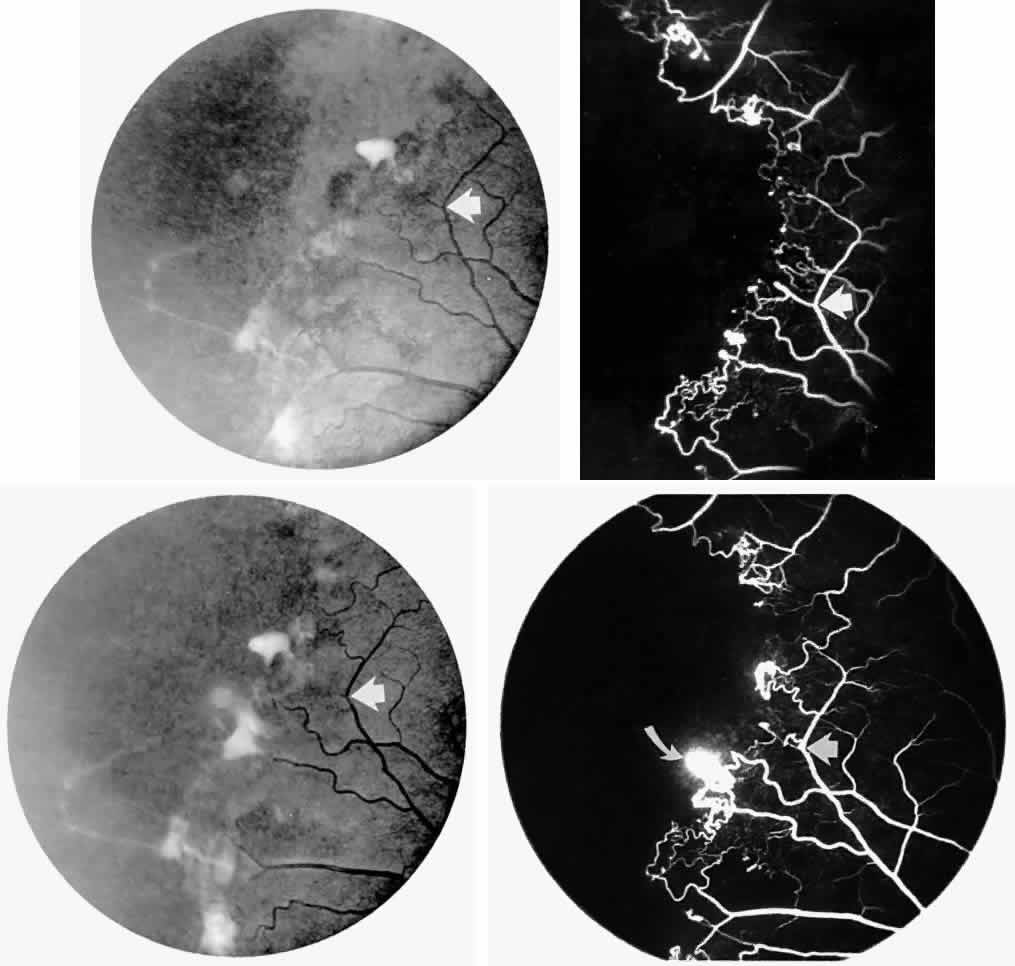

STAGE III: PRERETINAL NEOVASCULARIZATION (PROLIFERATIVE SICKLE RETINOPATHY). “Sea fan”-shaped neovascularization typically develops on the venular side of an arteriolar-venular anastomosis, mimicking the normal development of retinal capillaries (Fig. 24).125 A lowered oxygen tension and angiogenic factors released on the venular side may be the stimulus for neovascular growth.125,126 In most instances, the direction of growth is toward the ora serrata, from the perfused retina toward the nonperfused retina. Presumably, this represents an abortive attempt to revascularize the nonperfused retina, initiated by vasoproliferative factors.

Fig. 24. A. Photograph of the peripheral retina, demonstrating several small fibroglial membranes. B. Fluorescein angiogram corresponding to A, showing multiple arteriolar-venular anastomoses with early sea fan formation. C. Photograph of the same area 2 years later demonstrates more fibroglial membranes. D. Fluorescein angiogram corresponding to C shows new sea fans caused by an arteriolar-venular anastomosis (curved arrow). Large arrow (A through D) identifies corresponding arteriolar bifurcation.

The characteristic neovascular lesions of PSR are called sea fans because they resemble the marine invertebrate Gorgonia flabellum.70 They tend to occur more commonly in the temporal periphery, but they have been reported to occur in the temporal macula in the presence of extensive nonperfusion.130,133 Initially they grow on the surface of the retina, but they often become elevated into the vitreous and adhere to a partially detached posterior hyaloid.114 It may be difficult to visualize small sea fans ophthalmoscopically; however, fluorescein angiography clearly demonstrates leakage of dye into the vitreous (Fig. 25). The feeding arteriole is usually more tortuous than the draining venule (Fig. 26). Early on, the neovascular lesion is fed by a single arteriole and drained by a single venule, but with time, additional arterioles and venules become arborized within the lesion (Fig. 27).129 Growth of the sea fan often occurs circumferentially, rather than radiallyÜmh- 1Ý, toward the ora serrata. Progressive circumferential growth may lead to neovascular lesions extending around the entire periphery. As it matures, a white fibroglial mantle often covers the neovascular tissue (Color Plate 2B).

Fig. 25. Fluorescein angiogram of early proliferative sickle retinopathy arising from an arteriolar-venular anastomosis in an area of irregular peripheral capillary border. Note that this area of qualitatively abnormal peripheral capillary border is in the same eye with a qualitatively normal peripheral retinal vasculature, as demonstrated in Figure 23.

Fig. 26. A. Arterial filling phase of the fluorescein angiogram of a sea fan demonstrates tortuosity of the feeding arteriole. B. Early arteriolar-venular filling phase demonstrates straightening of the draining venule. Note that this sea fan is adjacent to the qualitatively normal peripheral retinal vasculature demonstrated in Figure 23.